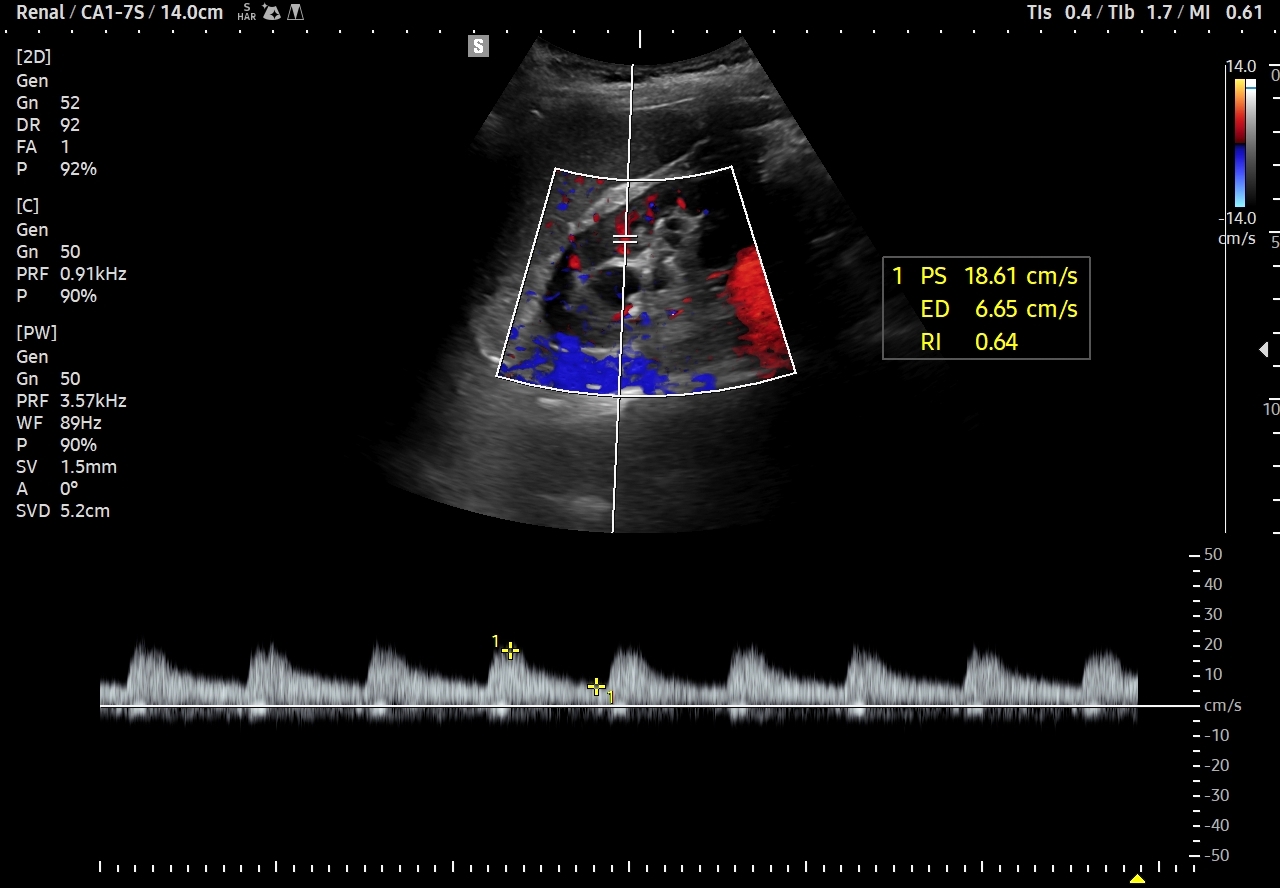

W badaniu USG ogniska endometriozy zwykle przyjmują formę hypoechogennych guzków i nieregularnych mas; mogą być niejednorodne echogenicznie i zawierać drobne obszary torbielowate; w trybie color-Doppler i MVI wykazują skąpe unaczynienie.

Na skanach w niniejszym artykule zaprezentowany jest przypadek endometriozy głębokiej w miednicy mniejszej z intraluminalnym nacieczeniem dystalnego odcinka moczowodu, jego całkowitą niedrożnością i wtórnym wodonerczem. Choroba w tak zaawansowanym stadium wykryta została przypadkowo w rutynowym przezbrzusznym badaniu USG jamy brzusznej. W ramach diagnostyki różnicowej przeprowadzone zostały badanie CT, MRI oraz ureterocystoskopia z pobraniem materiału do badania histopatologicznego, na podstawie którego postawiono rozpoznanie endometriozy.